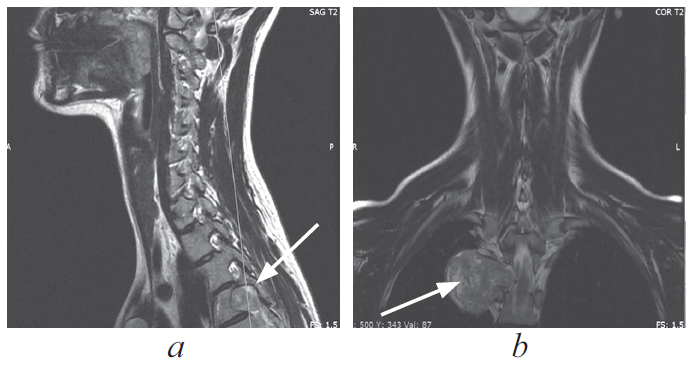

По данным магнитно-резонансной томографии грудного отдела позвоночника паравертебрально справа на уровне тел позвонков Th5 визуализируется образование гантелеобразной формы, размерами 9 × 39 × 35 мм, исходящее из правого корешка Th5; правое межпозвонковое отверстие расширено (рис. 1, 2).

Рис. 2. Магнитно-резонансная томограмма грудного отдела позвоночника, сагиттальная (a) и коронарная (b) проекции, опухоль указана стрелками

Fig. 2. MRI of the thoracic spine, sagittal (a) and coronal (b) projections, the tumor is indicated by arrows